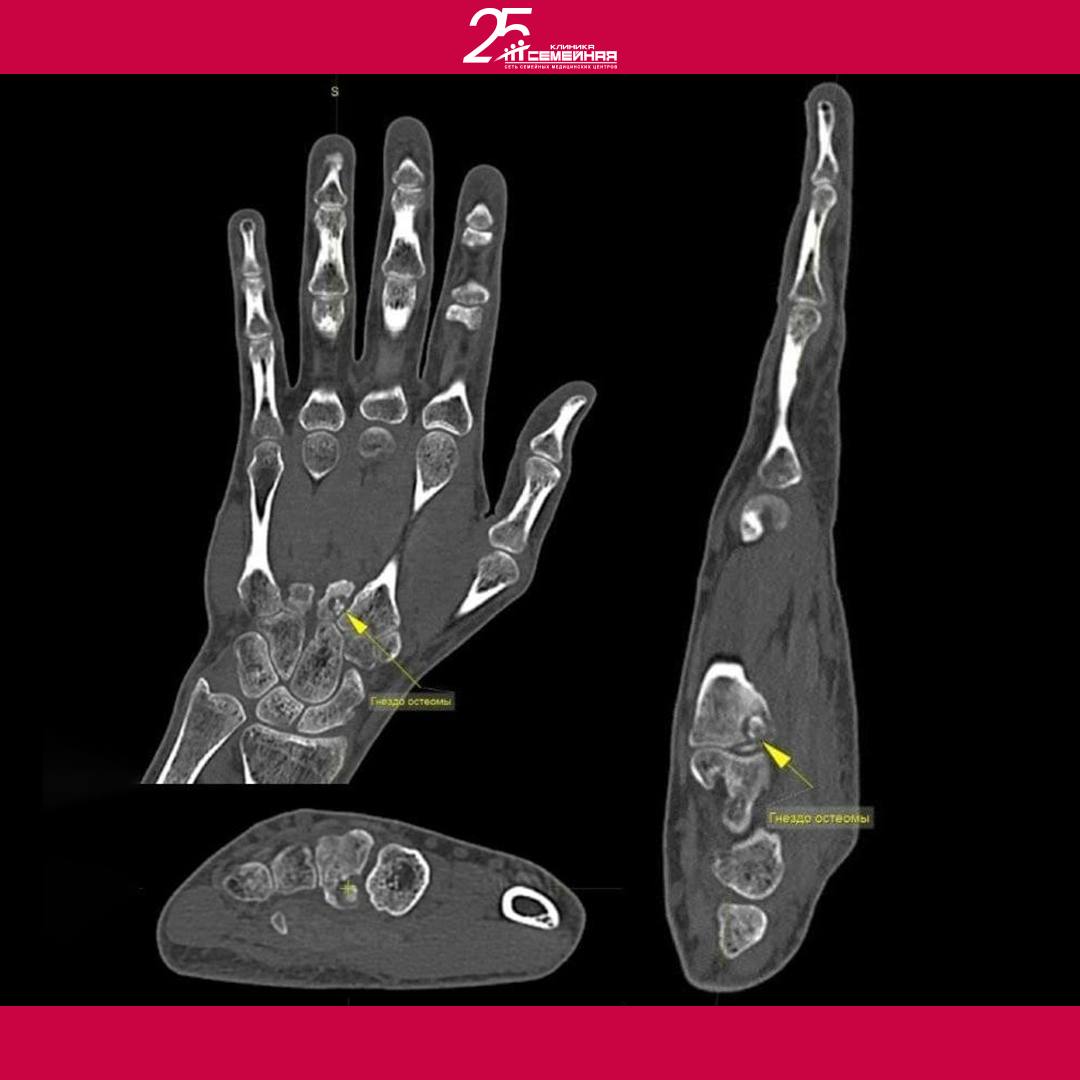

Тогда Ойбек Тургунхужаев вместе с Сиденковым Андреем Юрьевичем − травматологом-ортопедом решили выполнить МРТ и МСКТ кисти.

Травматолог-ортопед Сиденков Андрей по данным МРТ и МСКТ диагностировал отек 3 пястной кости − остеоид-остеому левой кисти.

Это доброкачественная, медленно развивающаяся опухоль кости, ведущим симптомом которой является выраженная боль по ночам, интенсивность которой нарастает по мере развития опухоли.